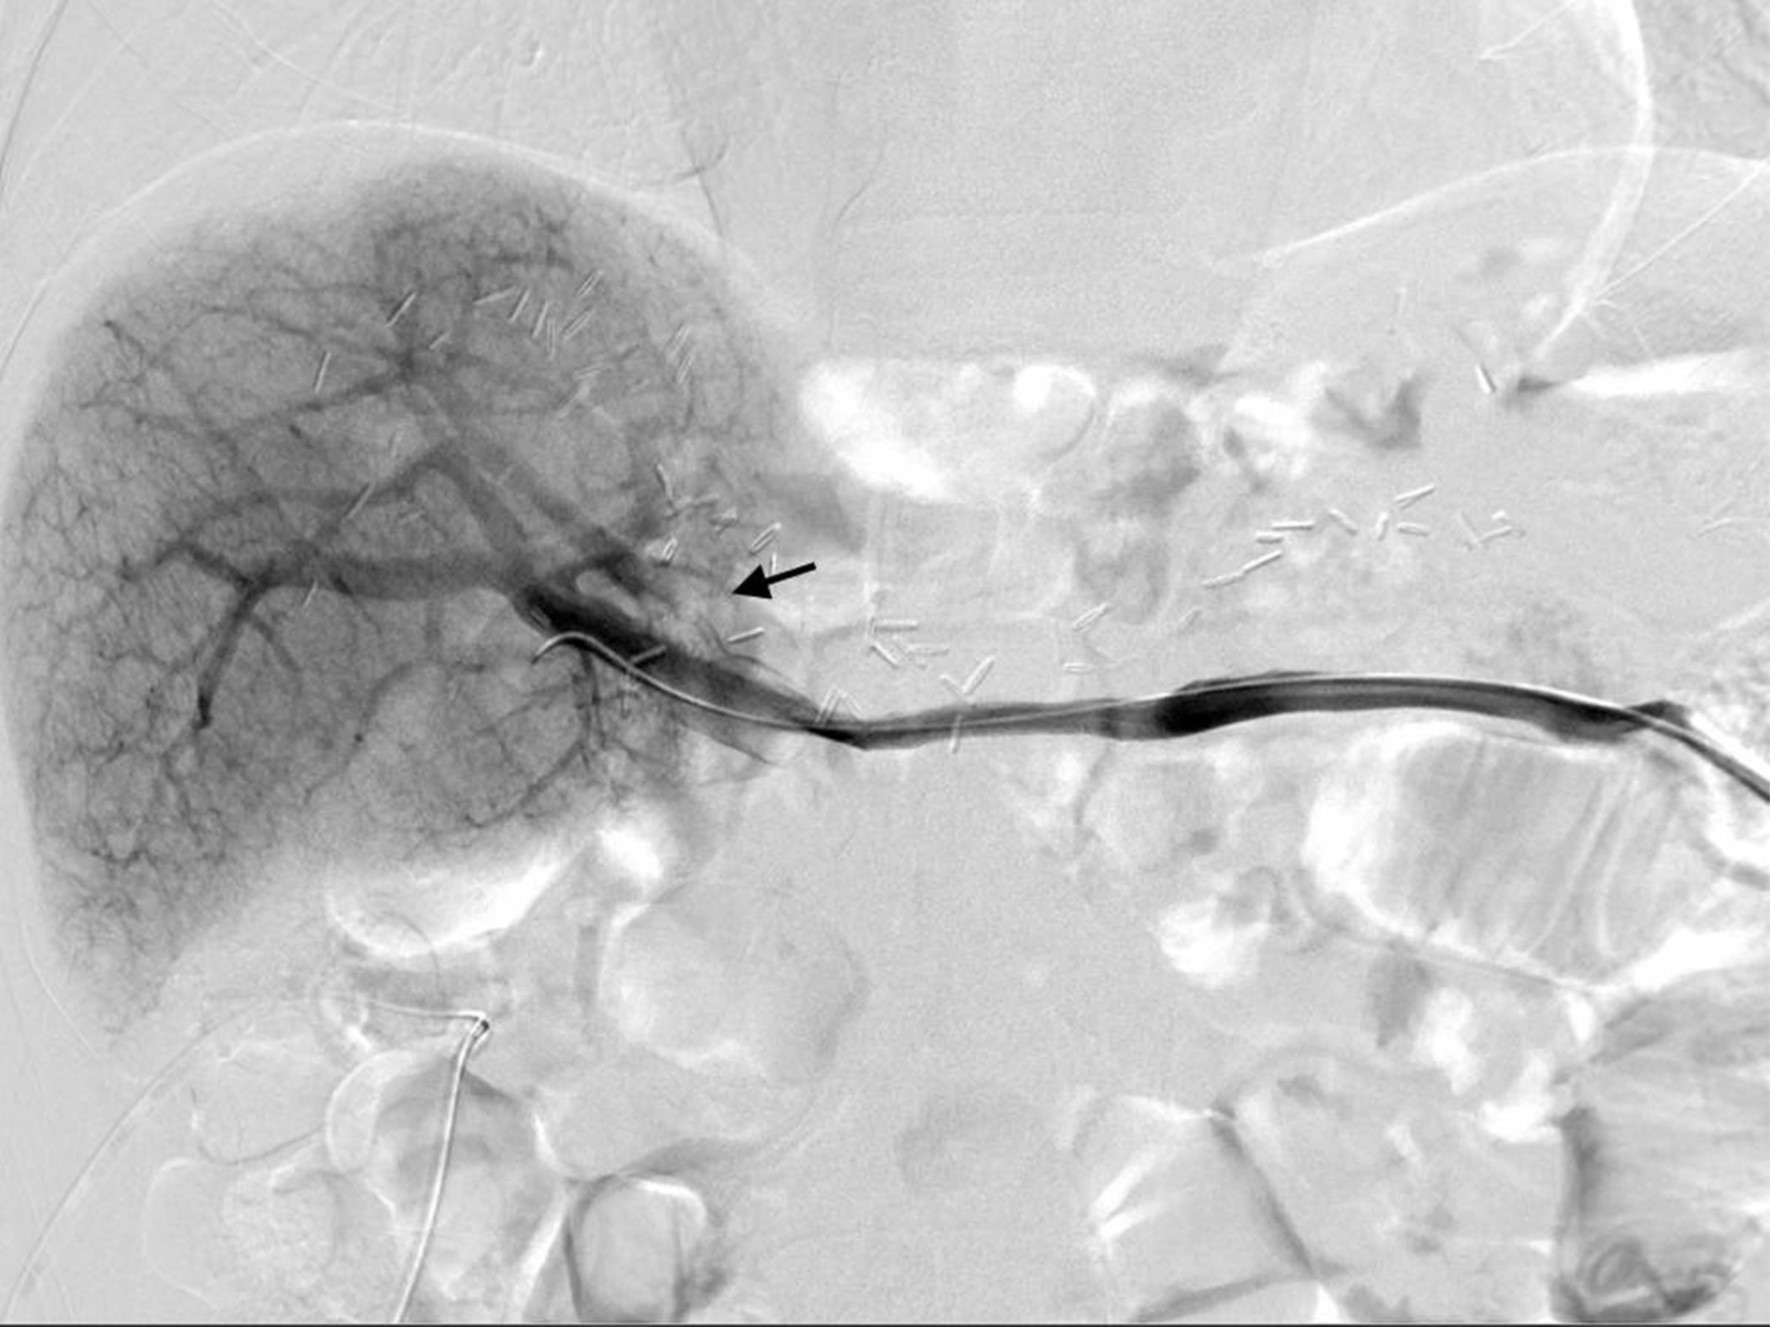

초음파 유도하에 비장정맥(splenic vein)을 천자하여, 8Fr sheath를 삽입하였음. Sheath를 통한 간문맥조영술(splenoportography)에서, 우전문맥(right anterior portal vein)의 심한 협착을 확인하였음(Fig. 2A). 이후 guidewire를 사용하여 우전문맥을 선택한 뒤, 6x40mm의 Stent(Zilver; Cook Medical, Bloomington, IN)를 삽입하였고, 남은 병변에 대해서 6x40mm balloon(Ultrathin Diamond;Boston Scientific, Natric, MA)을 이용하여 혈관성형술을 시행하였음. 이후 시행한 간문맥 조영술(Portal venography)에서 협착의 호전을 확인할 수 있었음(Fig. 2B). 삽입한 sheath의 지혈을 위해서, Histoacry(N-butyl-cyanoacrylate, B.Braun,Germany)과 lipiodol(Lipiodol Ultrafluid, Andre Guerbet, Aulnay-sous-bois, France)의 혼합(mixture, 1:4) 2cc로 tract embolization한 후 시술을 종료하였음.

Fig. 2. B

Fig. 2B Right ant.Portal vein stenosis was resolved after stent placement and PTA.